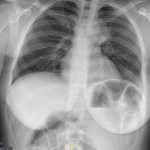

Caso 31

Jose Herrero Martinez